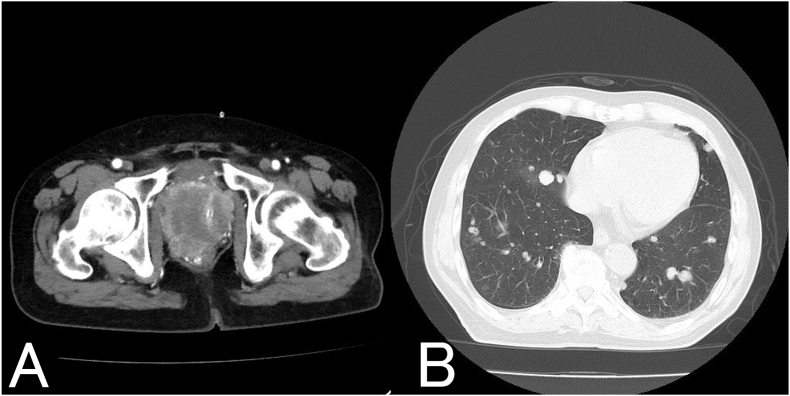

我们报告的情况下,85岁的男子诊断为转移性前列腺癌三年前。在联合雄激素阻断治疗期间,他出现了血尿、便血和疲劳。这些症状归因于前列腺癌的局部进展和不适当的抗利尿激素分泌综合征(SIADH)。限水、姑息性放疗和托伐普坦均可缓解症状。4个月后,由于高钙血症,他出现食欲不振和疲劳,最终被诊断为恶性体液性高钙血症(HHM)。

We report the case of an 85-year-old man diagnosed with metastatic prostate cancer three years earlier. While on combined androgen blockade, he developed hematuria, hematochezia, and fatigue. These symptoms were attributed to local progression of prostate cancer and syndrome of inappropriate antidiuretic hormone secretion (SIADH). Water restriction, palliative radiation, and tolvaptan alleviated the symptoms. Four months later, he experienced appetite loss and fatigue due to hypercalcemia, ultimately leading to a diagnosis of humoral hypercalcemia of malignancy (HHM).